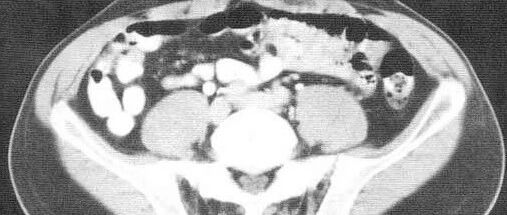

外科医生阅片能力——盆部CT